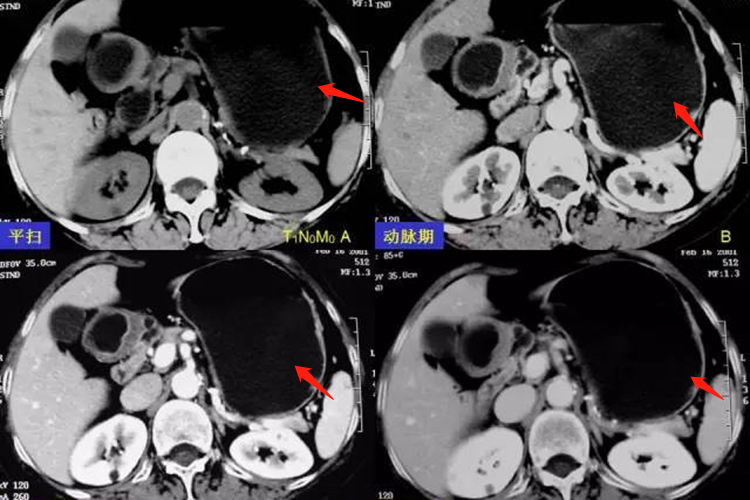

胃癌的CT表现主要是胃壁局限性增厚,表面不光滑,增强早期(动脉期)和增强晚期(静脉期或实质期)都有强化。